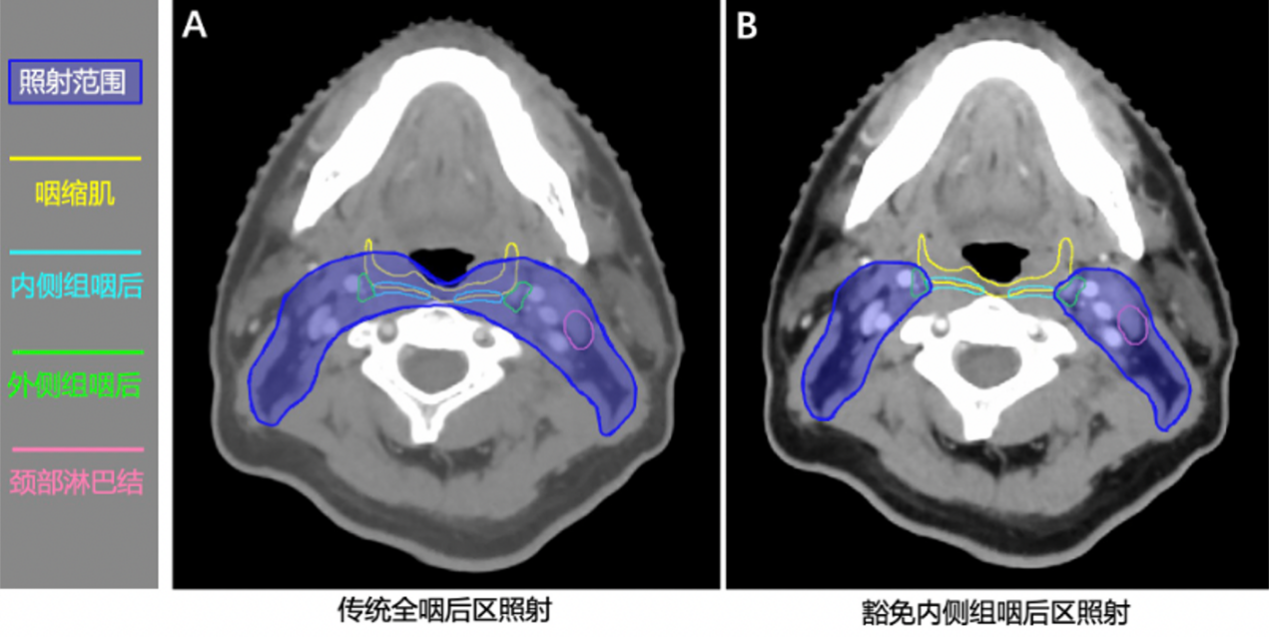

既往国内外指南推荐的全咽后淋巴结区预防照射是初诊无转移鼻咽癌的标准放疗方式,其照射范围过大,导致与之毗邻的吞咽相关结构(如咽缩肌、声门上喉等)受照剂量过高,吞咽困难发生率高达35.4%,甚至引发部分患者的误吸(66.9%)、吸入性肺炎(12%)、鼻饲或胃造瘘饮食(10%)等严重后果,严重影响患者的生活质量。前期研究团队基于高分辨率MRI的精准影像发现,尽管鼻咽癌咽后淋巴结转移发生率高,但主要集中于外侧组,内侧组极为少见(0.6%)。这一发现为缩小靶区范围提供了重要的理论依据。基于此,团队提出科学假设:豁免内侧组咽后区照射,可在不影响肿瘤局部控制率的前提下,降低咽缩肌的受照剂量,进而减少吞咽困难的发生。

图1:内侧组咽后区豁免放疗新技术